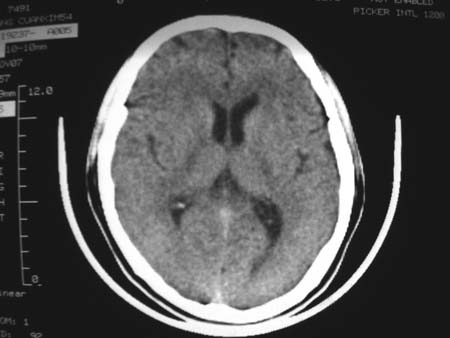

男,54岁,十天前被钢管打伤头顶部,现自述头部不适,视物模糊,并于两天前发觉右枕部有包块,既往未有明显异常.

颅骨多处骨质不完整,内板变薄,右侧额颞部局部呈“穿凿样”骨质缺损,相应区硬膜外密度略增高。多考虑:骨嗜酸性肉芽肿!

颅骨多处骨质不完整,内板变薄,右侧额颞部局部呈“穿凿样”骨质缺损,相应区硬膜外密度略增高。多考虑:骨髓瘤或骨嗜酸性肉芽肿!

颅骨多处骨质不完整,内板变薄,右侧额颞部局部呈“穿凿样”骨质缺损,缺损骨质边缘锐利无硬化,相应区硬膜外密度略增高。多考虑:骨嗜酸性肉芽肿!

颅骨多处骨质不完整,内板变薄,右侧额颞部局部呈“穿凿样”骨质缺损,相应区硬膜外密度略增高。多考虑:骨髓瘤或骨嗜酸性肉芽肿!10天前受伤,不会在2天前才发现头部包块,估计与外伤无关.